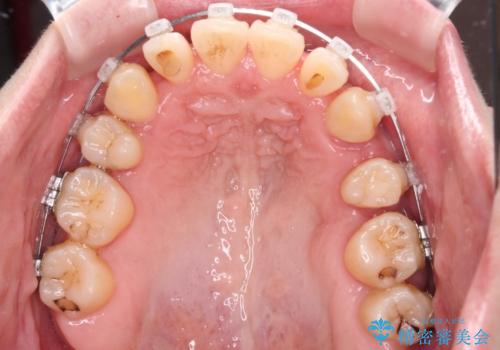

- クリアブラケット

- 上下前歯のデコボコを気にして来院された患者様です。

デコボコが強いため、非抜歯で矯正をすると出っ歯仕上がりとなるため、上下左右の第一小臼歯4本を抜歯することとしました。

治療期間全体を通して歯の移動スピードがゆっくりであったので、当初予定よりも1年ほど長い、3年間を要することとなりました。